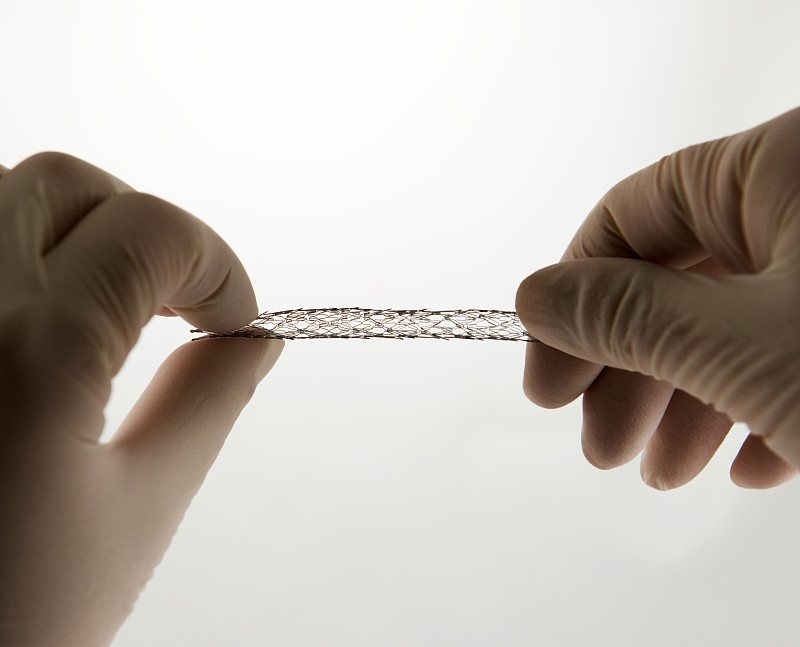

冠状动脉支架医疗详情

血管内手术用支架详情

冠状动脉支架医疗详情

支架血管成形术的概念详情